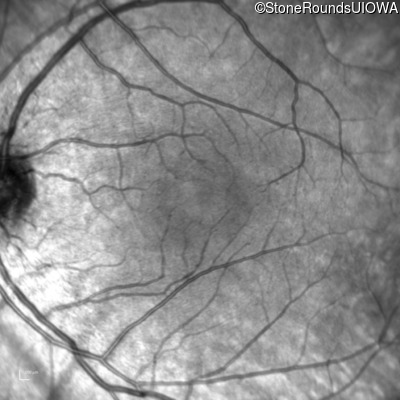

Infrared Fundus Photograph - Right - 20/25

Exemplar